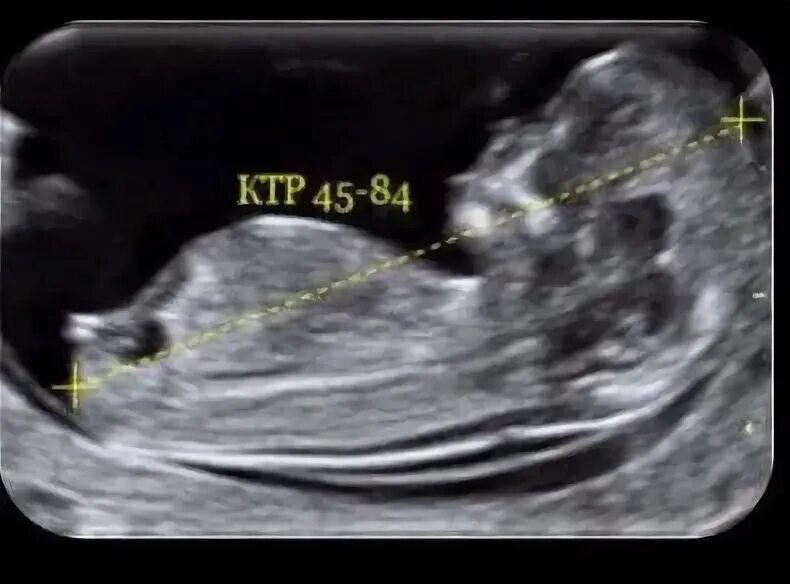

Что такое ктр на узи при беременности